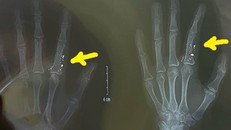

(Ngày Nay) - Suýt phải cắt bỏ một phần tay do nhiễm độc thuỷ ngân từ nhiệt kế vỡ, đâm trực tiếp vào ngón tay, nữ bệnh nhân đã được các bác sĩ bệnh viện Bạch Mai chuẩn đoán và cứu chữa kịp thời.